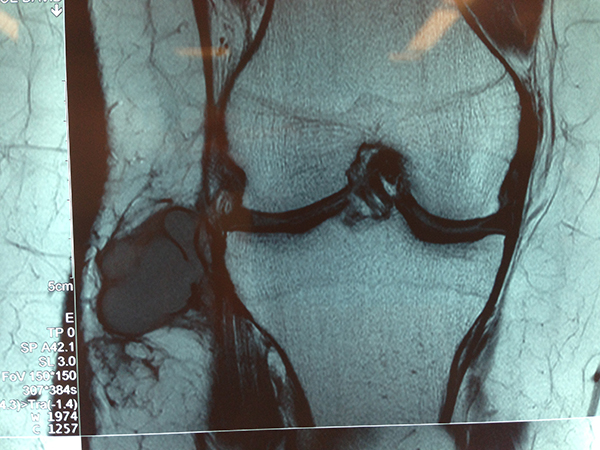

MRI Of Lateral Parameniscal Cyst

Imaging of the Knee with Chronic Instability

These are the imaging techniques and measurements I use for reliability and simplicity and the benefit they provide in decision making.

- X-rays These can show, Patella alta, Trochlea dysplasia

- CT scans – CT scans have been widely used in the assessment of chronic instability. I mainly use CT scan to assess complex rotational alignment deformity

- Magnetic Resonance Imaging (MRI) – MRI scans will reliably demonstrate

Bone abnormalities – Trochlea and patella dysplasia

Large cartilage injuries to the patellofemoral region

Patella tilt any abnormalities to the static constraints e.g. medial patellofemoral ligament rupture and patella alta

Bone bruising of a recent dislocation will be seen on these images

Although far more expensive, MRI is more effective than CT scanning in determining if patellar chondral lesions are present and for determining cartilage thickness and volume. Assessment of patellar cartilage thickness and volume is important to evaluate for osteoarthritis.

Axial views on MRI or CT scans may be used to evaluate the trochlea-tubercle (TTTG) distance. This is the horizontal distance in a vertical plane between the intercondylar notch and the tibial tubercle. Similar to the Q-angle, this evaluates the potential laterally directed vectors on the patella. Some authors suggest that a distance of 2 cm is specific, but not sensitive, for maltracking.

MRI Lateral Parameniscal Cyst